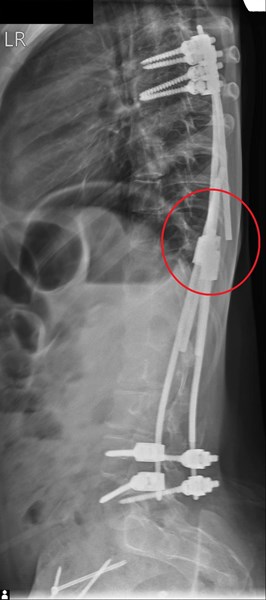

След извършване на клиничен преглед и необходимите образни изследвания става ясно, че имплантираната система е компрометирана и една от пръчките е счупена. В този случай, освен силната болка, която детето изпитва, съществуват рискове от настъпване на редица усложнения като – неврологични усложнения (пареза, парализа), псевдоартроза (несрастване на костта), прогресия на гръбначната деформация, инфекции и др. Това налага системата да бъде ревизирана и изцяло сменена в много кратки срокове.

Проф. Яблански и неговият екип извършват ревизията и сменят компрометираната стабилизация, като поставят окончателна такава, чрез задна вертебродеза (Spinal Fusion) -„златен“ стандарт при хирургично лечение на деца със сколиоза в световен мащаб. При сливане (Fusion) на гръбначния стълб, изкривените прешлени зарастват заедно, за да създадат единична солидна кост в парвилна позиция.

Екипът установява и миграция на имплантираните винтове, в областта на тазобедрените стави, което ще наложи поредно хирургично лечение в областта на по-късен етап.